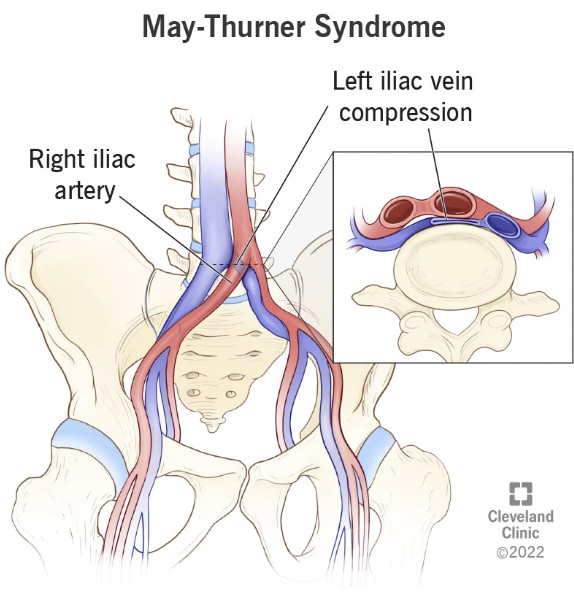

•Many of the debilitating complications of the COVID-19 vaccine appear to result from the iliac vein (which governs venous return from the legs and pelvis) becoming compressed and its blood supply becoming significantly obstructed (which in turn gives rise to numerous characteristic symptoms that can be recognized once one knows to look for them). More importantly, this compression can often onset quite suddenly and patients remember the exact moment that compression occurred.

•A condition known as May-Thurner syndrome affects slightly over 20% of the population. In it, the (high pressure) right common iliac artery overlies and compresses the (low pressure) left common iliac vein against the lumbar spine

Normally, individuals with this syndrome do not notice it, but in some cases it can predispose them to unexpected blood clots (due to venous return being obstructed).

•Dr. Vaughan believes that the (well-documented) damage the spike protein causes to walls of the blood vessels weakens the iliac vein enough that pressure from the iliac artery can cause it to collapse. In turn, he has collected compelling radiography to prove it.

•If an iliac vein compression is treated with anticoagulation, this typically improves the symptoms of it, but once the anticoagulants are stopped, the symptoms return (as the source of the clotting has not been addressed). For this reason, iliac vein compressions are often treated with stenting, which some patients (but not all) have reported significant benefit from.

Once I heard Dr. Vaughan's lecture, I realized his hypothesis tied together many observations I'd made over the years and likewise explained many of the successes I had come across in vaccine injured patients after manual therapists worked on a patients hip socket and then had (intentionally or unintentionally) had partially decompressed the iliac vein, creating a dramatic "inexplicable" improvement in the patient's condition.